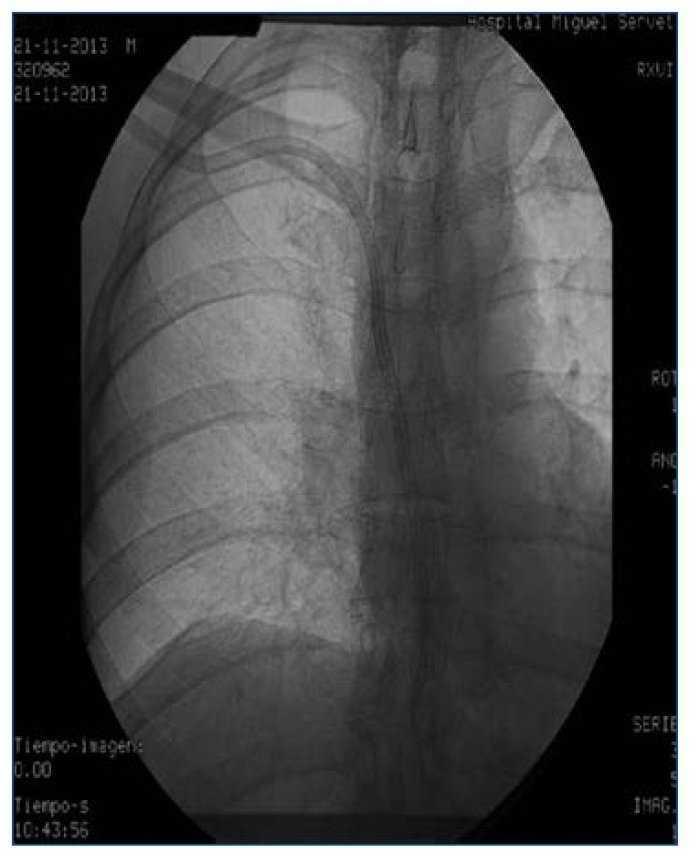

Figura 1.

Presentamos el caso de una paciente en hemodiálisis, que había agotado todas las posibilidades de realización de FAVI y que se dializaba a través de catéter yugular tunelizado colocado en yugular interna derecha. Anteriormente había sido portadora de varios catéteres en vena yugular derecha e izquierda y en ambas femorales, habiendo desarrollado trombosis de estas como complicación asociada. Por malfuncionamiento del catéter yugular derecho se realiza cavografía, que muestra trombosis oclusiva de toda la vena cava superior con gran hipertrofia de la vena ácigos (figura 1). Se intenta abordaje por vía yugular derecha, que es imposible debido a su trombosis, por lo que se realiza abordaje subclavio derecho y se consigue implantar el catéter dejando el extremo distal próximo al cayado de la ácigos (figura 2). La paciente se dializó a través de este catéter sin incidencias, con flujos de 300-350 ml/min consiguiéndose un KTV medio de 1,64 durante 4 meses, momento en que fue sometida a un trasplante renal de donante cadáver. La colocación de catéteres en la vena ácigos está descrita en numerosas ocasiones como complicación del procedimiento en el abordaje de accesos vasculares subclavios o yugulares. Sin embargo, con nuestro caso mostramos que la vena ácigos puede ser una alternativa válida como acceso venoso central funcionante, con buenos flujos y buena calidad de diálisis en pacientes con trombosis en los territorios venosos habituales.